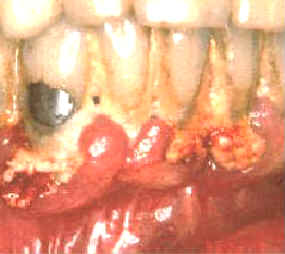

El margen gingival de la mandíbula esta  intensamente inflamado y el tejido exhibe señales de daño severo. En ciertas áreas del margen gingival se observan áreas de necrosis . El margen gingival se encuentra retraído por la gran cantidad de placa bacteriana y debido a esta acumulación de placa dental hay bolsas poco  profundas. Las bacterias y las reacciones del huésped han causado un movimiento apical del epitelio de unión con la cosnecuente pérdida de inserción . En este caso particular el diagnóstico de las lesiones es fácil.

Estas imágenes muestran inmediatamente como queda luego de la limpieza con instrumental  ultrasónico. La gingiva se desprende del diente y la mayoría del epitelio de la bolsa periodontal queda expuesto. El  sangrado durante el tratamiento es intenso y el paciente suele notar algún sangrado post operatorio de la encía. Los tejidos blandos suelen molestar.

Durante algunos días el paciente al comer y cepillar sus dientes, puede presentar síntomas de dolor y sangrado. Suele ocurrir  bacteremia  durante el tratamiento y durante algunos días posteriores debido al cepillado dental. El tejido conjuntivo expuesto y el epitelio frágil permiten el pasaje de las bacterias orales a los vasos sanguíneos. Deben administrarse antibióticos  en forma profiláctica  en los  pacientes  que presentan condiciones sistémicas riesgosas si ocurriera una bacteremia.